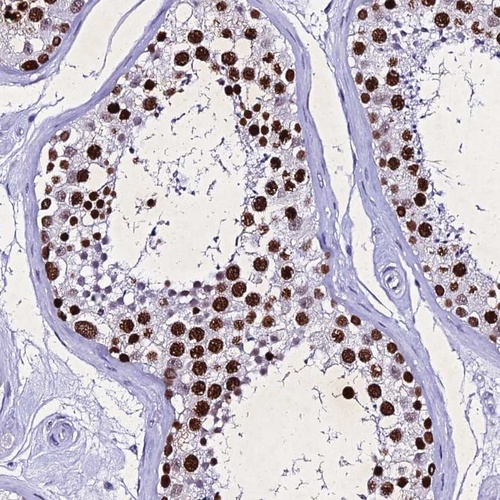

Immunohistochemical staining of human testis shows strong nuclear positivity in cells in seminiferus ducts.